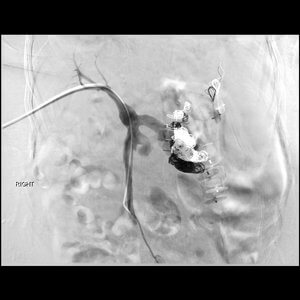

50 year old female patient s/p liver transplant presents with persistent encephalopathy. A massively dilated splenorenal shunt was identified but an attempted BRTO procedure failed. The patient presents for transhepatic embolization.

Comment: This patient had gradually progressing and increasingly severe and prolonged episodes of encephalopathy after liver transplantation. As it turns out, there was a significant splenorenal shunt that was likely responsible for this. An attempt was made at an outside hospital to perform retrograde embolization via the left renal vein but the large size of the varices made that ineffective. As a result, we attempted to access the splenorenal shunt using a transhepatic approach. Once the portal vein was catheterized, a venogram demonstrated hepatofugal flow with preferential flow into the splenorenal shunt. We were then able to catheterize the shunt and embolize the major branches. Following embolization, hepatopetal flow was restored.